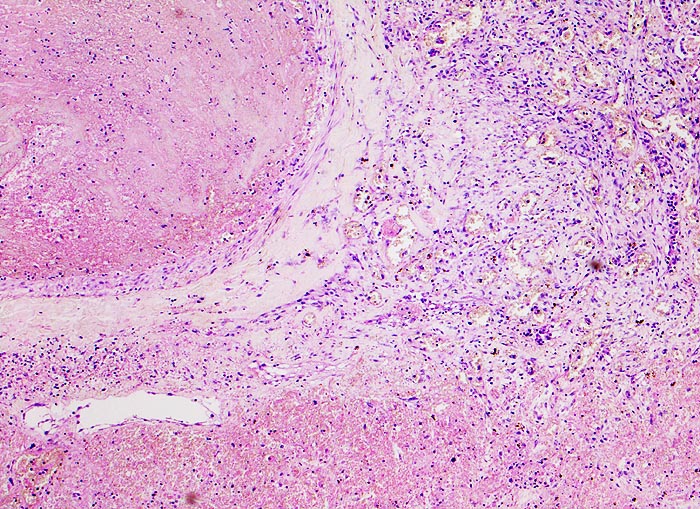

Morphologische Merkmale:

- Scharf begrenzte dreiecksförmige hämorrhagische Nekrose des Lungenparenchyms.

- Alveolen gefüllt mit zerfallenden Erythrozyten, Kerntrümmern und Fibrin.

- Lungengerüst erhalten im Randbereich der Nekrose, nicht mehr erkennbar im Zentrum.

- Abgeblasste Zellkerne in der Nekrosezone.

- Pulmonalarterienast mit nicht wandhaftendem Thrombembolus am Rand des Infarktes.

- Frischblut im Lumen des begleitenden Bronchiolus.

- Pulmonalarterienast mit Strickleiter.